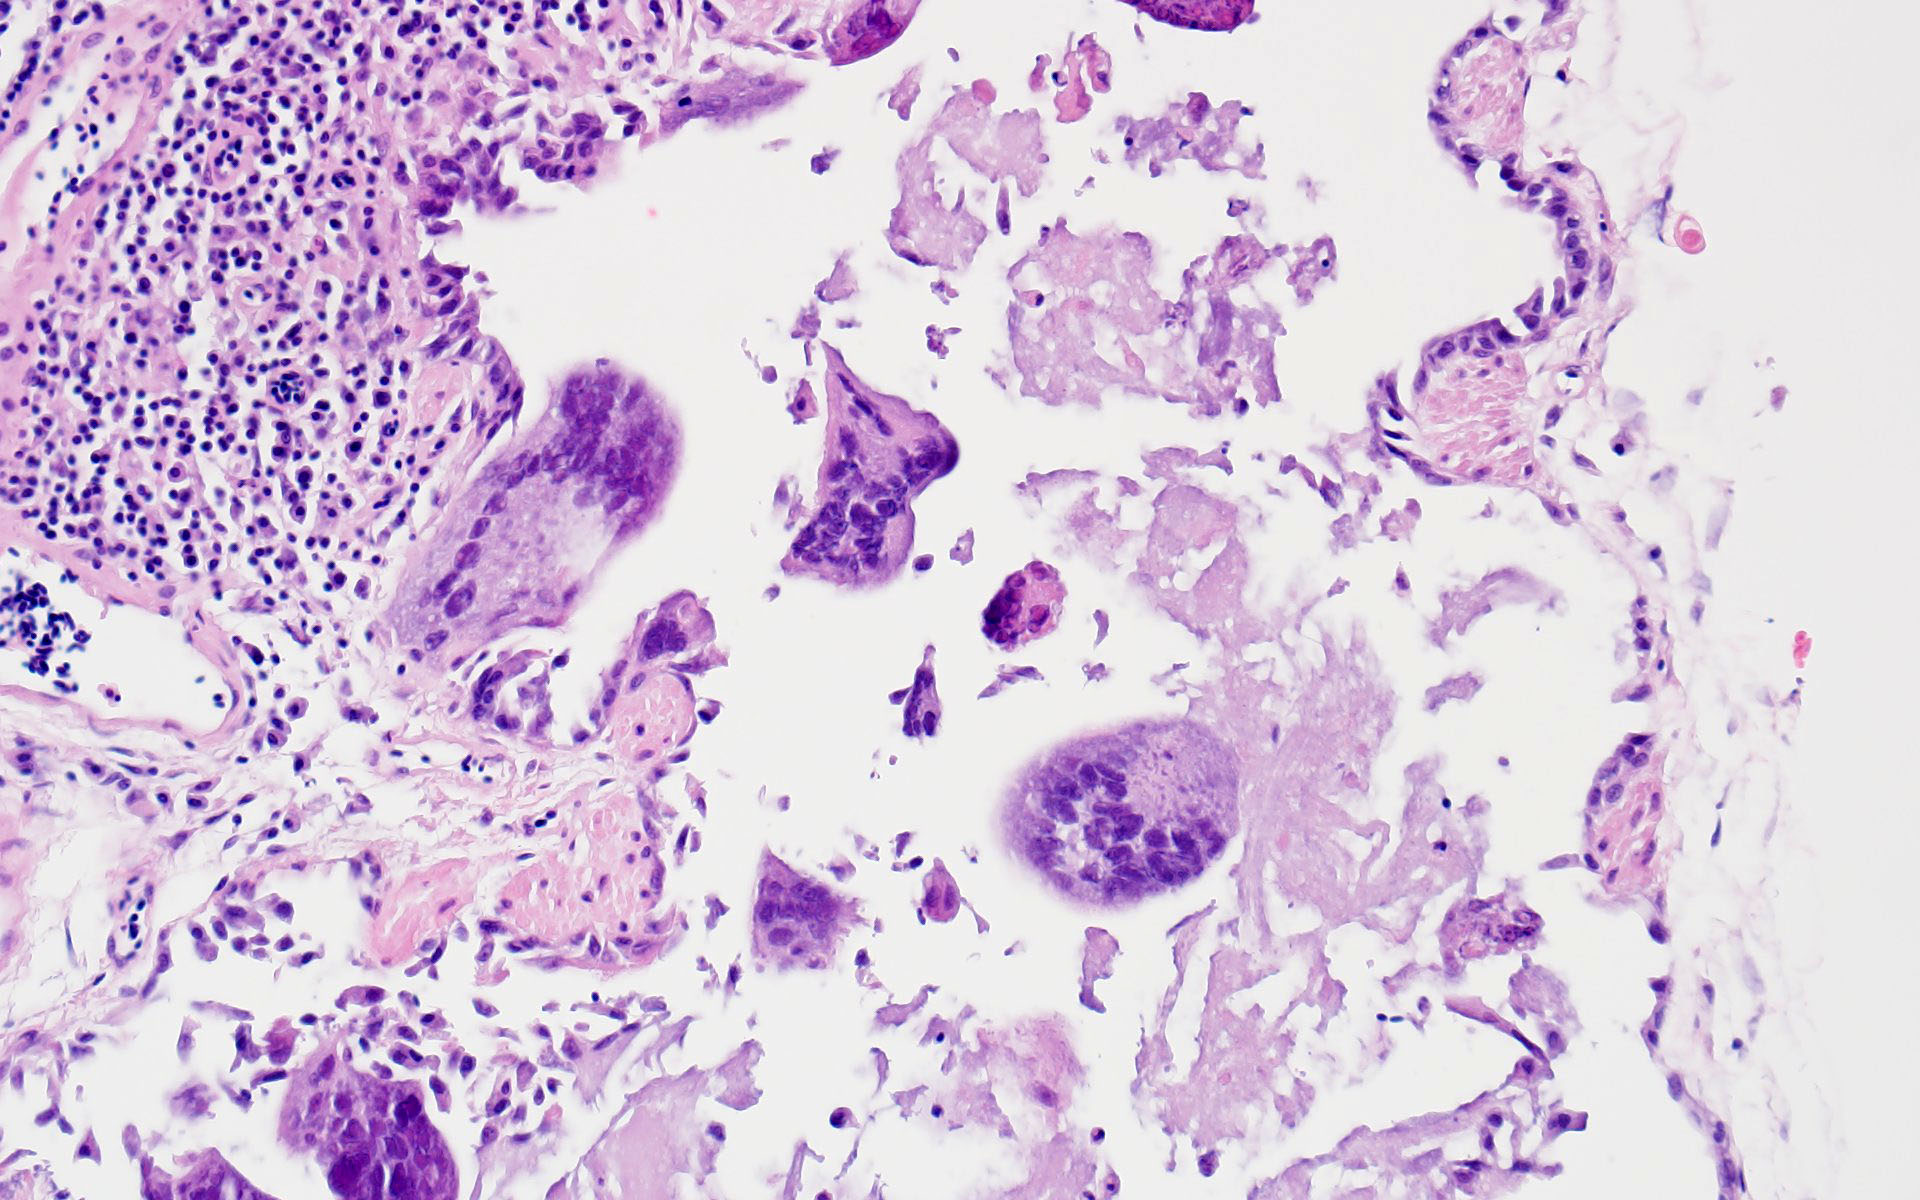

Microscopic Description:

The bronchi and parabronchi contain numerous large syncytia with large amphophilic-to-eosinophilic intranuclear inclusions that marginalize the chromatin. Bronchi and parabronchi also often contain foamy macrophages, pale basophilic mucus, homogeneously eosinophilic edema fluid, fibrin, cellular debris, and sloughed necrotic epithelial cells.

- Tubular reproductive tract, air sac, lung: Epithelial necrosis, acute, multifocal, moderate, with intranuclear viral inclusions and numerous syncytia.

The JPC’s own Dr. Elise LaDouceur moder-ated this year’s avian-focused seventeenth conference. This first case provided participants with a panoply/salmagundi/”dog’s breakfast” of tissues to sort through to achieve a diagnosis. The characteristic intranuclear viral inclusion bodies of herpesvirus were best seen in the air sac respiratory epithelium, which also rewarded conference-goers with some exceptional viral syncytia. Of the potential herpesviral culprits, psittacine al-phaherpesviruses (PsAHV) 1, 3, and 5 have been reported in psittacine species, including Indian ringneck parakeets, and PsAHV-5 was isolated by the contributor in this case. The contributor provided some beautiful electron microscopy (EM) photos from this bird that demonstrated intranuclear herpesviral virions, with some virions budding from the nuclear envelope to become enveloped themselves, and others hanging around the rough endo-plasmic reticulum (RER) to acquire additional proteins. The JPC is grateful to the contributor for providing these excellent educational images!

In addition to the respiratory epithelium, a tubular structure adjacent to the ovary was also affected by PsAHV-5 (i.e., had syncytia and epithelial necrosis). The smooth muscle wall and cellularity of this structure is consistent with either oviduct or remnant Wolffian duct. This suggests that PsAHV-5 may have a broader epitheliotropism beyond respiratory epithelium.